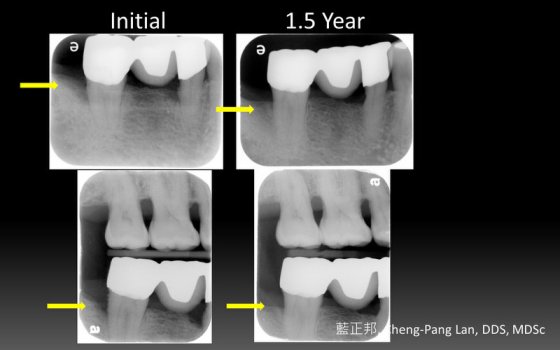

●第八章就是Buser最著名的Early implant placement in the esthetic zone,完整分類風險等級、挑選案例、單顆植體、多顆植體的前牙手術考量。更加入了超過十年的術後追蹤。我認爲Buser在這塊領域的貢獻非凡,是整本書的精華所在。